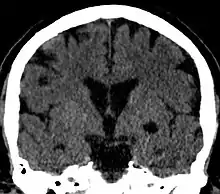

Coronal CT of the brain showing a choroidal fissure cyst

A choroidal fissure cyst is a cyst at the level of the choroidal fissure of the brain. They are usually asymptomatic and do not require treatment.